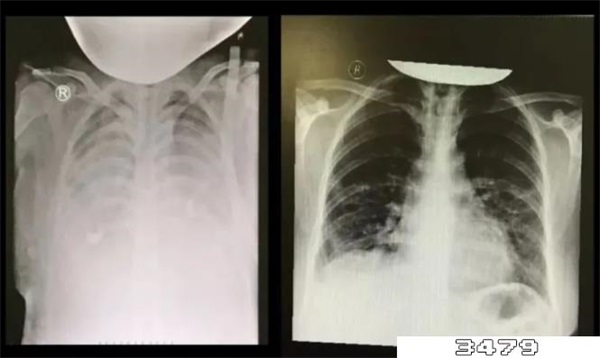

白肺并不是专业医学名词或者疾病,而是医务人员对肺部显影形态的一种叫法。当肺泡里出现炎症、病毒感染甚至是肺部肿瘤,有渗出液和炎性细胞时,肺泡透光性会变差,做CT或X线检查时射线无法穿透,就会在影像上显影出白色区域,临床上把白色影像区面积达到70%~80%的情况叫做“白肺”。

简单来说,如果患者的肺部出现感染、肿瘤或其他问题,就会发生异常病变,在CT或X光片上会呈现出肺部白化的情况,当这种肺部白化的区域面积达到一定程度时就属于“白肺”。需要注意的是,白肺并非新冠特有症状,其他呼吸系统疾病一样有可能引起白肺。